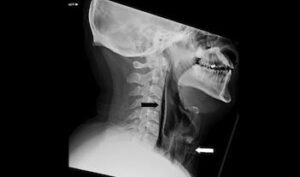

Röntgen çekildikten sonra, “cerrahi amfizem” adı verilen ve havanın kişinin vücudundaki en derin dokunun altında sıkışıp kalabildiği bir rahatsızlığı olduğu anlaşıldı. Hava, adamın boynundaki omurların yanı sıra göğsü ile akciğerleri arasındaki boşlukta sıkışıp kalmıştı.